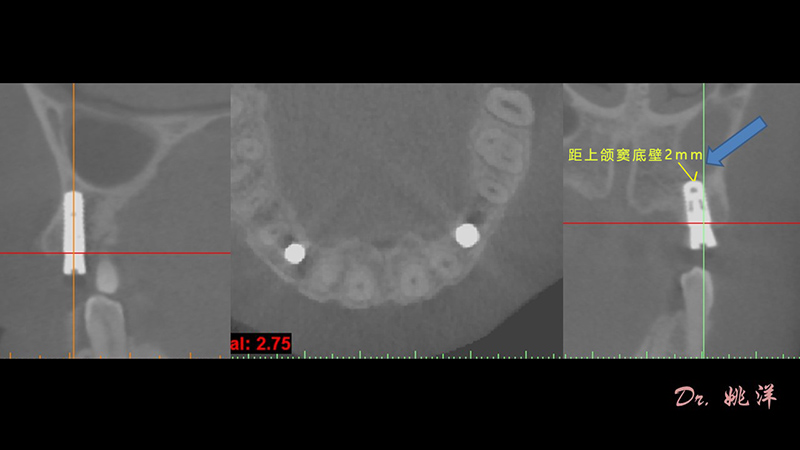

根據(jù)患者CT顯示,使用種植導(dǎo)航軟件設(shè)術(shù)前手術(shù)方案??紤]到患者拒絕手術(shù)摘除上頜竇囊腫等因素,此次手術(shù)選用了Straumann骨水平4.10*8.0mm的植體,植體末端位點設(shè)計距上頜竇底壁2mm處的同時兼顧種植方向和修復(fù)間隙,來達(dá)到理想的效果。

導(dǎo)航下精細(xì)分配修復(fù)間隙,精細(xì)規(guī)劃植入方向,避開上頜竇底,精確植入

從術(shù)后CBCT顯示可以看出,手術(shù)操作中完美地避開上頜竇底,并兼顧了正確的種植方向和修復(fù)間隙